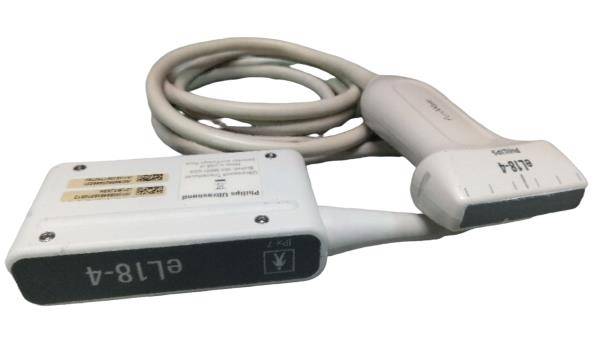

Save $ 674.82

DIAGNOSTIC ULTRASOUND MACHINES FOR SALE

Chison ECO1 Portable Ultrasound Machine, Quality, LED, Linear & Printer Included

Sale price$ 3,074.18

Regular price$ 3,749.00